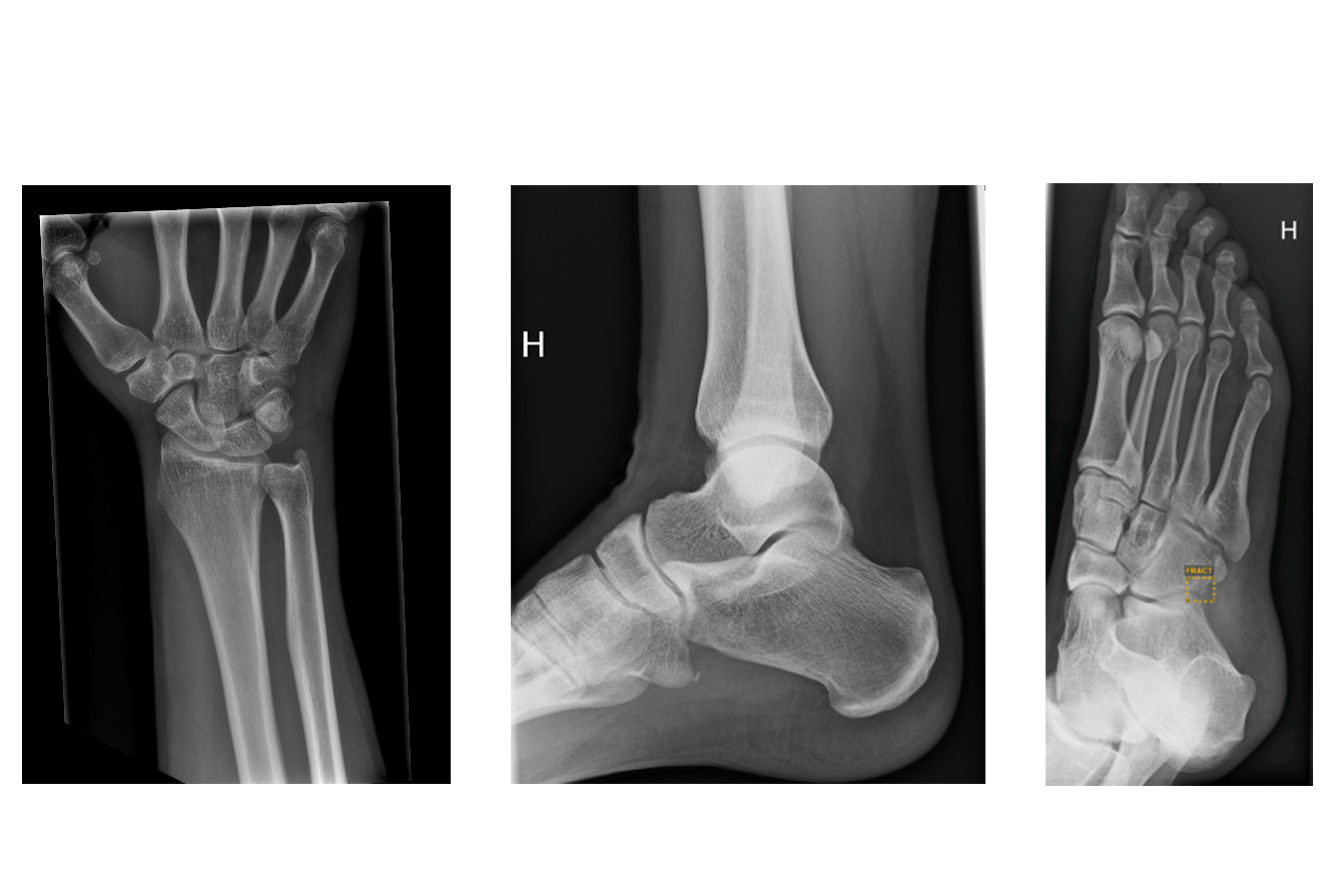

- Dagens medisin - Her er første fot som er diagnostisert med kunstig intelligens i Vestre Viken

- TV2 - Finner brudd som legene overser. Først i Norge med å teste dette

- VG - Fikk hånden analysert av kunstig intelligens - resultatet kom så raskt

- Eikerbladet - Line fra Ormåsen er den første i landet